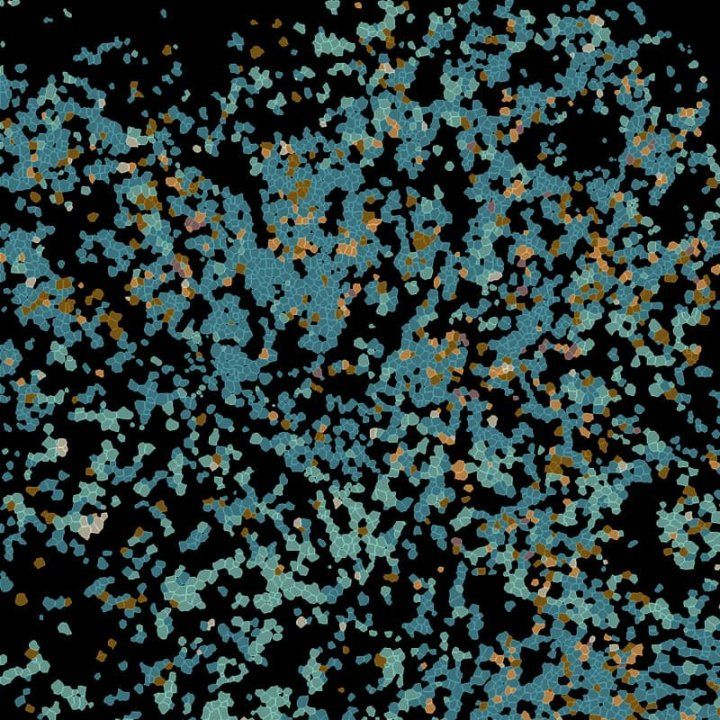

Imaging of cells in lymp nodes. Cells are blue and tan, indicating a different cell type

The authors used a new tissue imaging technique to identify each cell in the lymph node and to measure its activation and function. This image shows various types of immune cells in the lymph node, each colored based on its cell type. Image by Spitzer Lab